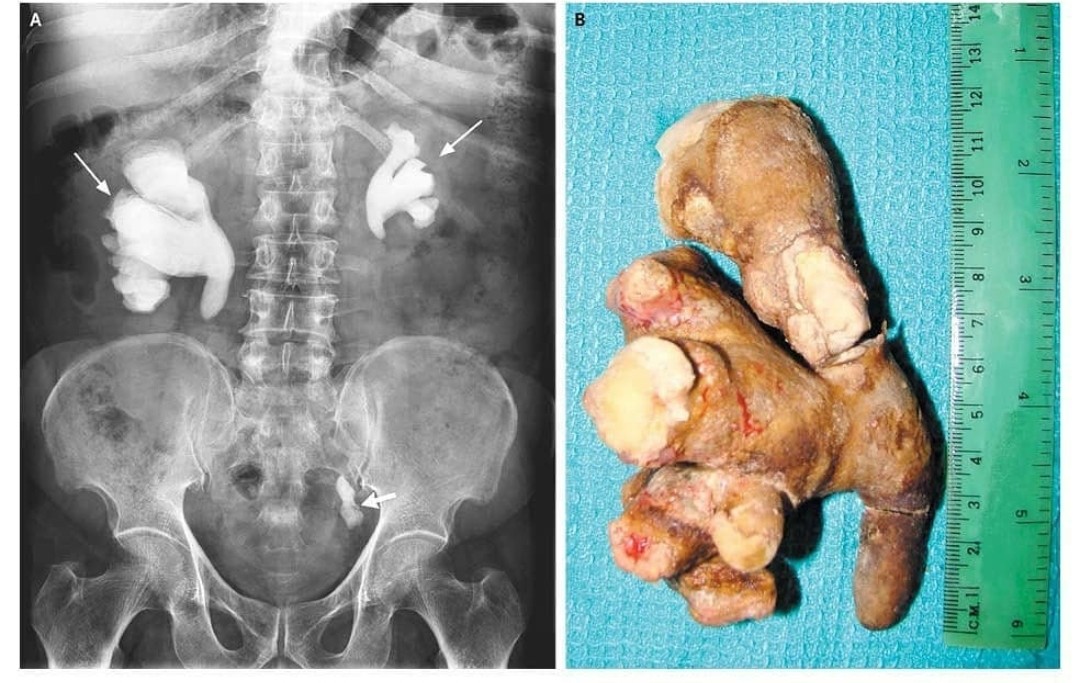

【画像】世界最大の尿管結石デカすぎワロタ

【画像】世界最大の尿管結石デカすぎワロタ

この腎盂いうとこ目一杯詰まってるってことやんな?

バラバラなってへんってことはこっち側アウト

もう1個で今後頑張ってくださいってことちゃうの?!

この腎盂いうとこ目一杯詰まってるってことやんな?

バラバラなってへんってことはこっち側アウト

もう1個で今後頑張ってくださいってことちゃうの?!

5 風吹けば名無し 2022/04/13(水) 00:48:39.27 ID:bYIllMEZ0

ショック死不可避

何があったんだよ

言うほど尿管までいけてるか?

こんなん出たら死ぬやろ

腎臓で型取りしてて草

尿道こわれる

こんなん尿が出なくなるやろ😰

どうやって取り出したんや

流石に腎臓死んどるやろ

これってこの大きさになるまで我慢したんか?

無痛だったとしか考えられん

腎臓内で定着した場合の結石の痛みは想像を絶する痛みなんやで

無痛だったとしか考えられん

腎臓内で定着した場合の結石の痛みは想像を絶する痛みなんやで